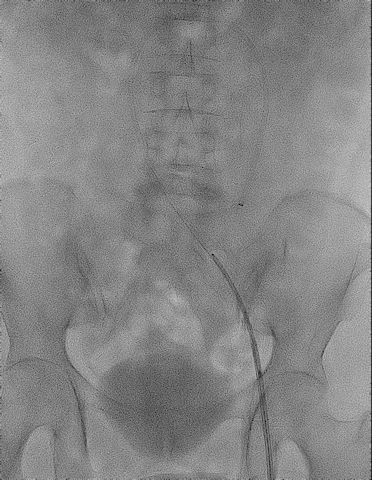

手术过程

手术过程(一):

超选左肾静脉,左侧卵巢静脉,造影见卵巢静脉曲张明显,直径13 mm,盆腔大量曲张静脉显影。